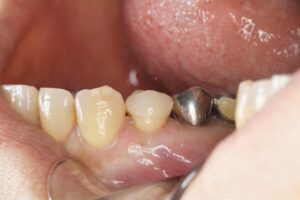

銀歯の下での虫歯の再発に対し、根管治療を歯内療法の専門医と連携しやり直し(自由診療)、その後セラミックで補綴処置を行なった。

さらに、土台を整えた後のジルコニアは、銀歯と比較して圧倒的に衛生的です。銀歯は経年劣化で変形し、セメントが溶け出した隙間から二次虫歯を招きやすいですが、ジルコニアは変質せず、汚れ(プラーク)も付着しにくい性質を持ちます。また、銀歯のように熱による膨張・収縮で歯にストレスをかけることもありません。

| 銀歯の下での虫歯の再発に対し、根管治療を歯内療法の専門医と連携しやり直し(自由診療)、その後セラミックで補綴処置を行なった。 |